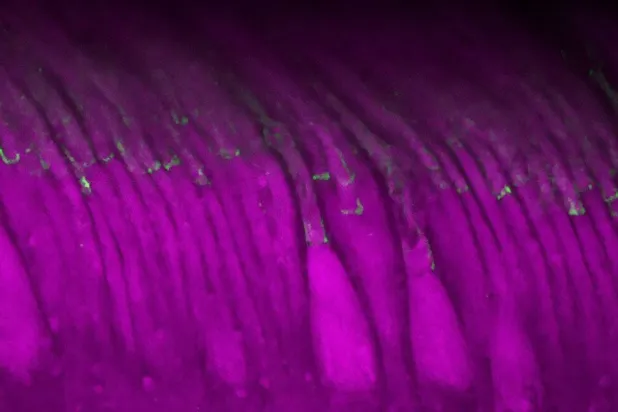

قد يبدو غبار الذهب في العين علاجاً غير مألوف، لكن دراسة جديدة أُجريت على الفئران في الولايات المتحدة تُظهر أن هذا النهج قد يُعالج التنكس البقعي.